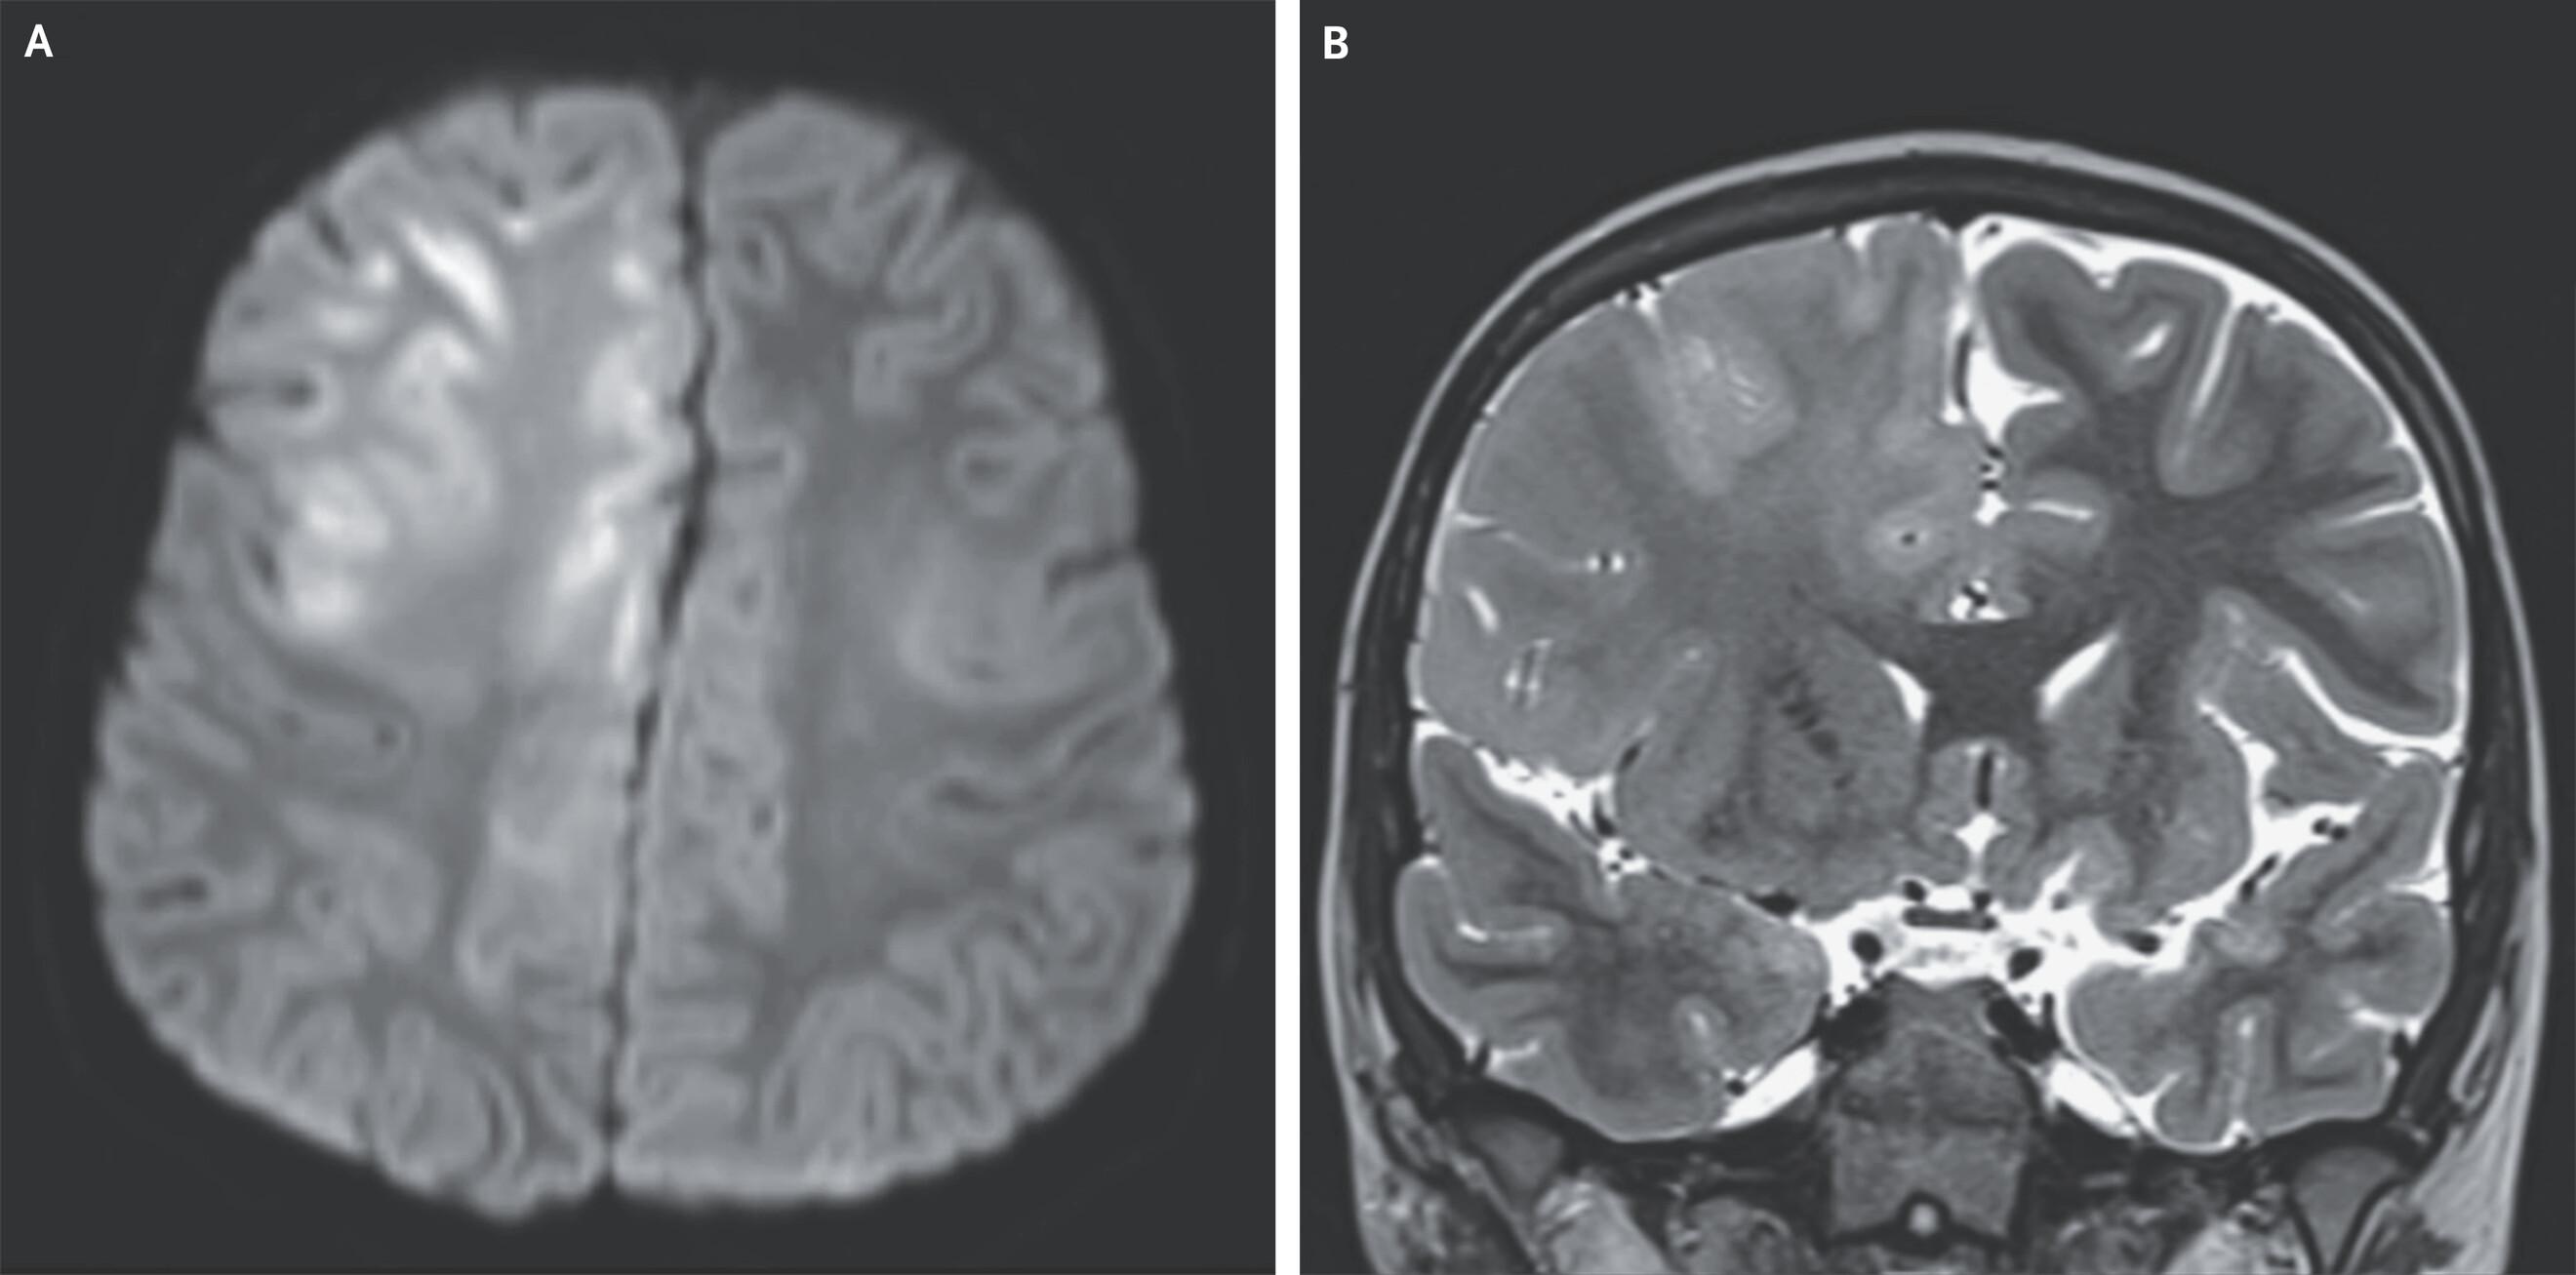

МРТ головного мозга показала отек и ограничение диффузии в лобных долях, которые охватывали кору и белое вещество, распространяясь в мозолистое тело. На электроэнцефалограмме (ЭЭГ) с обеих сторон медики также выявили комплексы Радермекера — так называют признаки на ЭЭГ, которые характерны для некоторых видов энцефалопатий.